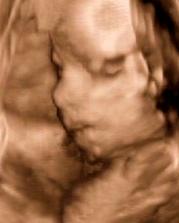

Naše bublinka

Náš svatební den byl 7.7.2007 a mimísek na sebe nenechal dlouho čekat 🙂 Už 21.8.2007 jsme na testu objevili // a těhu průkazku jsme dostali 12.10.2007. Naše bublinka by se měla narodit na konci dubna, tak uvidíme, kdy se jí bude chtít na svět.